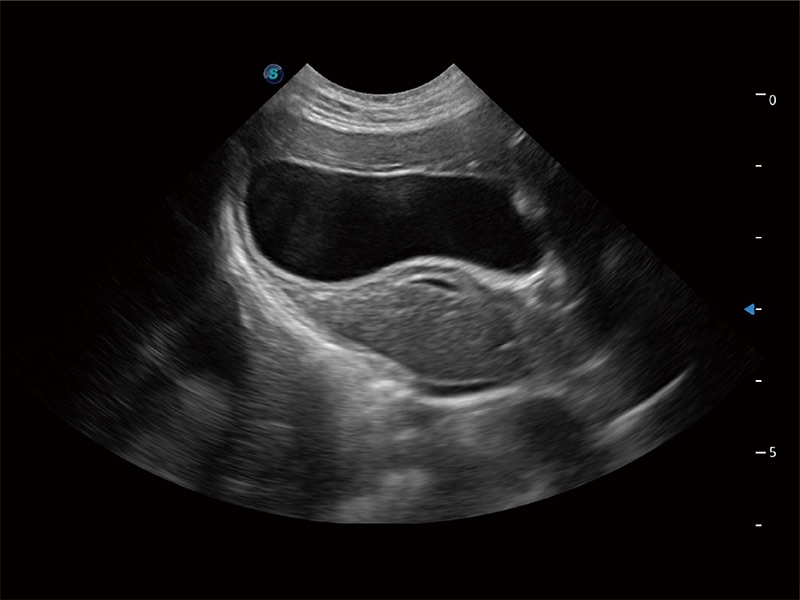

动物是人类最亲密的朋友和最值得信赖的伙伴。哈哈体育官网也一直致力于探索动物专用的超声影像解决方案。全新推出的ProPet系列,是哈哈体育官网在动物超声影像智能化、专业化、精准化的一次跨越式革新。动物不能用言语来表述自己的不适,通过超声影像,ProPet系列搭建了动物医生与不同物种沟通的“桥梁”,为动物医生注入了“治愈之力”。 ProPet 80 是哈哈体育官网匠心打造的一款高端动物专用彩超,采用性能卓越的全新硬件架构,极大提升超声系统的运行效率和数据处理能力,帮助动物医生从容应对日益增多的挑战性病例和日益多样化的临床需求。

高性能和先进的临床应用工具可以为动物医生提供临床信心。ProPet 80 搭载了先进的腹部和浅表应用工具,帮助医生在日常临床实践中发挥前所未有的作用。

一键自动识别膀胱壁及自动测量膀胱容积,不受膀胱形状和大小的限制,帮助医生快速精准获得测量的数据。